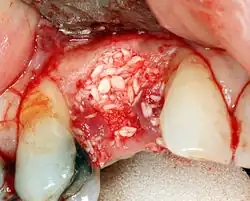

If bone width is inadequate it can be regrown using either artificial or cadaveric bone pieces to act as a scaffold for natural bone to grow around.

To achieve an adequate width and height of bone, various bone grafting techniques have been developed. The most frequently used is called guided bone graft augmentation where a defect is filled with either natural (harvested or autograft) bone or allograft (donor bone or synthetic bone substitute), covered with a semi-permeable membrane and allowed to heal. During the healing phase, natural bone replaces the graft, forming a new bony base for the implant.[56]: 223